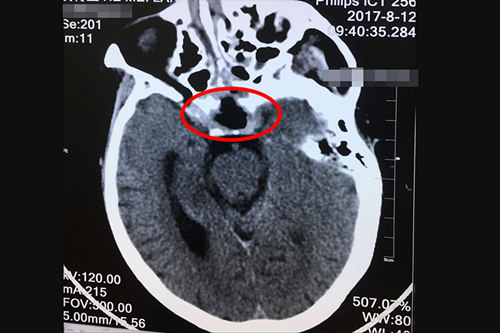

术前核磁共振显示:垂体巨大腺瘤(画圈部分)

家属抱着最后一丝希望,带着母亲来到上海,住院后,潘仁龙主任和科室其他专家对王老太的病情进行了充分探讨。大家一致认为:手术指征明显,只是因为瘤体较大,又靠近颈内动脉和大血管,给手术增加了很大难度。除此之外,患者还有贫血和三级高血压(很高危),这同样给手术带来挑战;为防止术中各种意外发生,应做好万全准备。

8月11日,王老太的“经鼻蝶垂体瘤显微切除术”在医院九楼手术室顺利进行。潘主任凭借着30多年熟练的临床经验,手术只用了不到两个小时,就切除了这个6公分的巨大肿瘤。